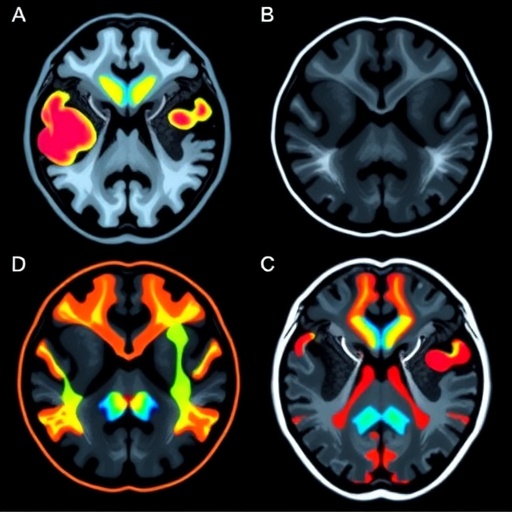

Complementing neuromelanin mapping is the T1w/T2w ratio imaging technique, which accentuates tissue contrast by dividing the signal intensities from T1-weighted and T2-weighted MRI sequences. This ratio has proven effective in delineating microstructural brain changes, including myelin density and iron deposition, which are altered in neurodegenerative diseases. When applied alongside neuromelanin-sensitive imaging, the combined approach enables a multidimensional characterization of brain pathology, capturing both neuronal loss and associated tissue integrity changes.

The researchers conducted a comprehensive analysis involving patients diagnosed with tremor-dominant PD and those with essential tremor, rigorously matched for clinical variables. Their neuroimaging protocol included high-resolution neuromelanin-sensitive sequences targeting the substantia nigra and locus coeruleus—another critical neuromelanin-containing area—combined with T1w/T2w ratio maps covering basal ganglia and cortical regions pertinent to motor control. Quantitative metrics were extracted, providing objective biomarkers reflective of the underlying neuropathology.

Findings revealed distinct neuromelanin signal attenuation in the substantia nigra of Parkinson’s patients compared to essential tremor subjects, consistent with selective dopaminergic neuron degeneration. Notably, the extent of neuromelanin loss showed a strong correlation with clinical measures of bradykinesia and rigidity, reinforcing its relevance as a PD-specific marker. On the other hand, essential tremor patients exhibited preserved neuromelanin signals but demonstrated subtle alterations in the T1w/T2w ratio within cerebellar regions, implicating cerebellar microstructural changes unique to ET pathophysiology.

Technically, the neuromelanin-sensitive sequences harness magnetization transfer contrast and optimized inversion recovery parameters to maximize contrast-to-noise ratio of neuromelanin-rich clusters. When fused with T1w/T2w ratio maps derived from standardized brain segmentation frameworks, the protocol offers reproducible, high-resolution brain images suitable for both clinical implementation and research investigations. Future refinements may integrate machine learning algorithms to automate region-of-interest delineation and enhance diagnostic accuracy.